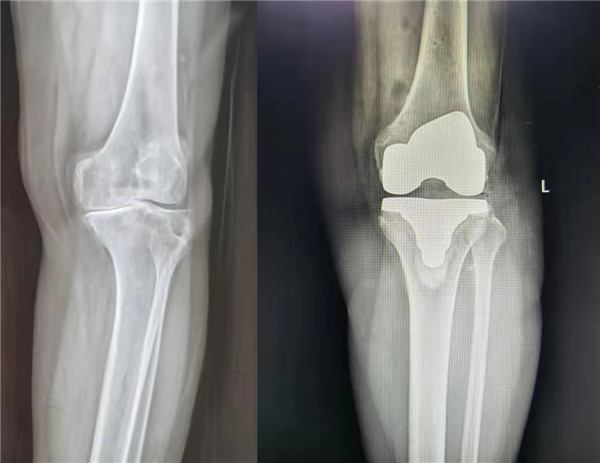

6月9日,由中华医学会骨科学分会候任主任委员、西安交通大学第二附属医院关节外科中心主任王坤正教授主刀,杨佩主任医师、王春生副主任医师、田润副研究员协助,成功完成了我国首例国产髋膝兼容关节手术机器人辅助全膝关节置换手术。

该手术使用的“ARTHROBOT”七轴髋膝兼容关节手术机器人,在术中可对膝关节活动度、下肢对线与关节间隙进行实时评估,依照术中实际情况实时调整规划方案,并按规划精准完成股骨与胫骨侧的截骨,误差控制在1mm与1˚范围以内,实现膝关节个性化、精准化手术治疗。